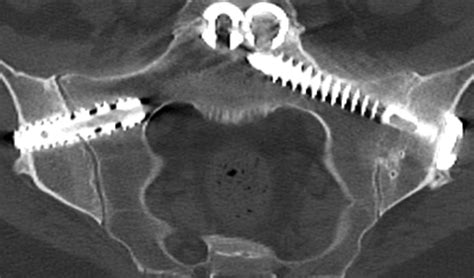

The most common and effective procedure for addressing SI joint pain is minimally invasive SI joint fusion. Unlike traditional open back surgeries that required large incisions and long hospital stays, modern Si Joint Surgery is performed using small incisions and specialized implants.

The surgery typically involves the following steps:

1. Anesthesia: The patient is placed under general or regional anesthesia.

2. Access: The surgeon makes a small, 2-to-3-centimeter incision in the buttock area.

3. Implant Placement: Guided by fluoroscopy (real-time X-ray imaging), the surgeon places titanium implants across the SI joint to bridge it.

4. Fusion: These implants hold the joint in a fixed, stable position, allowing the body to naturally grow bone across the joint, permanently fusing it.